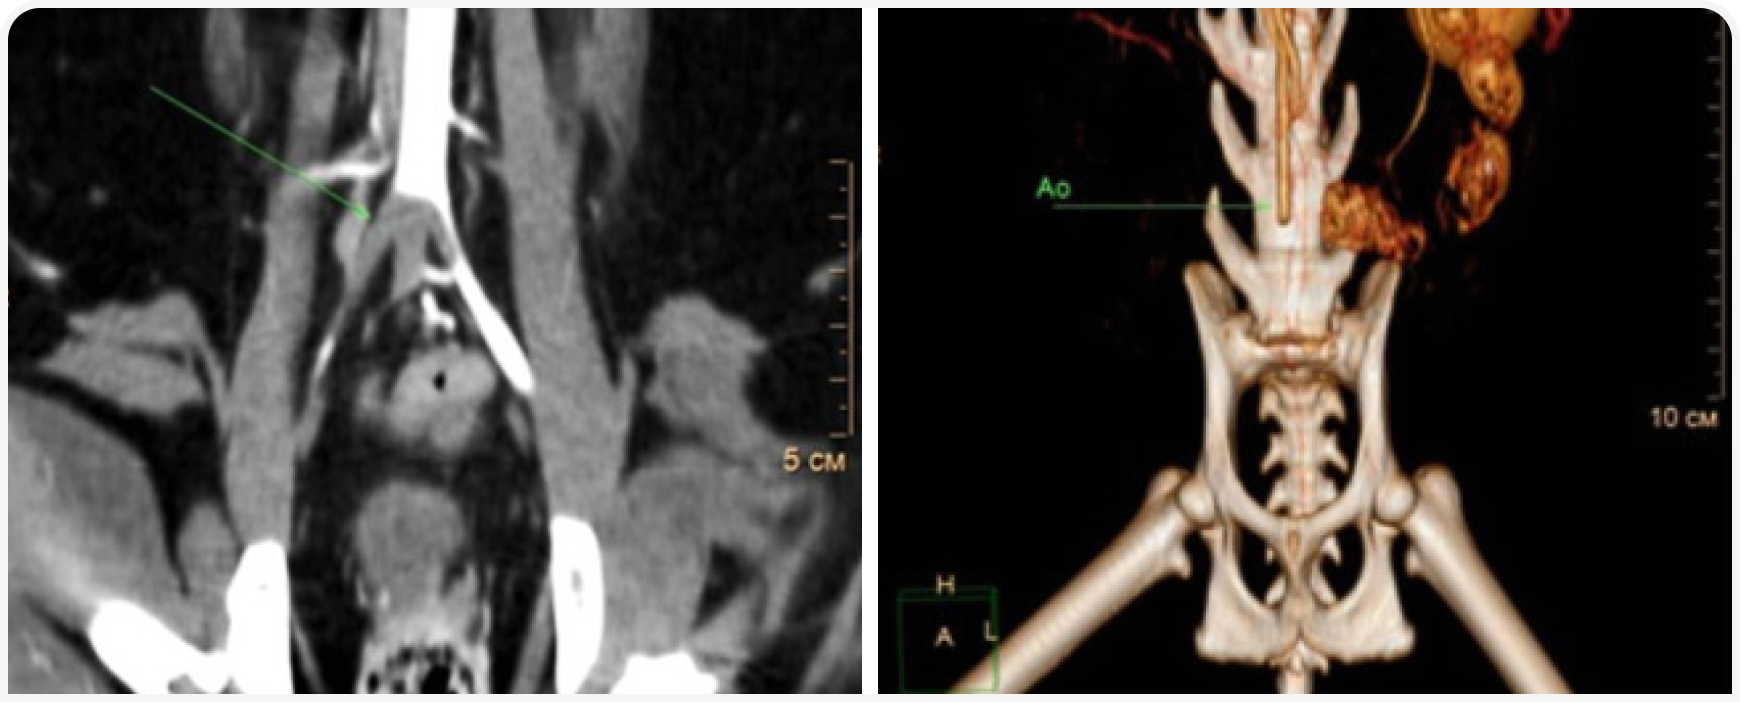

КТ-ангиография – наглядный метод диагностики, который может быть использован для демонстрации расположения тромба. По КТ-ангиографии оценивают дефект заполнения артериального сосуда контрастным веществом (рис. 7).

Помимо расположения самого тромба на КТ, необходимо исследовать другие ткани и органы на наличие дефектов контрастирования. В нашей практике у животных с ТЭК мы обнаруживали мелкие инфаркты коркового слоя почек, которые до этого не удавалось выявить на УЗИ (рис. 8), и сегментарный дефект распределения контраста в паренхиме селезенки.